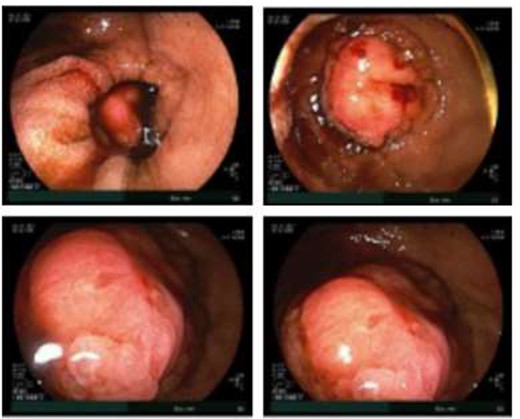

Given the patient’s anemia, melena and small bowel thickening, the patient was referred for upper and lower endoscopies, neither of which revealed the etiology of the patient’s symptoms. A pill endoscopy was also performed to evaluate the small intestine, though this was also unremarkable. The patient therefore underwent a double balloon enteroscopy, which was significant for a 3 cm small bowel mass located in the distal jejunum/proximal ileum (Fig. 2). The mass was biopsied and concerning for an adenocarcinoma. As a subsequent staging workup was negative for distant metastasis, the patient was taken for an exploratory laparotomy and small bowel resection. At the time of surgery, it was noted that the small bowel mass was located within an undiagnosed Meckel’s diverticulum (Fig. 3). The resected specimen was sent to pathology, which was significant for a moderately to poorly differentiated adenocarcinoma arising from a small bowel diverticulum, which was invading through the muscularis propria and into subserosal soft tissue with lymphovascular invasion (Fig. 4). The patient was therefore diagnosed with a Stage IIB (T4, N0) small bowel adenocarcinoma. After resection, the patient’s post-operative course was unremarkable, and he was discharged home on post-operative day 3. He was referred to medical oncology and is now receiving adjuvant capecitabine with oxaliplatin. As the patient’s resected specimen displayed negative margins, after completing the standard of care chemotherapy protocol, he will undergo active surveillance in accordance with the National Comprehensive Cancer Network guidelines.

Gross pathology images of the bowel mass located within a Meckel’s diverticulum.